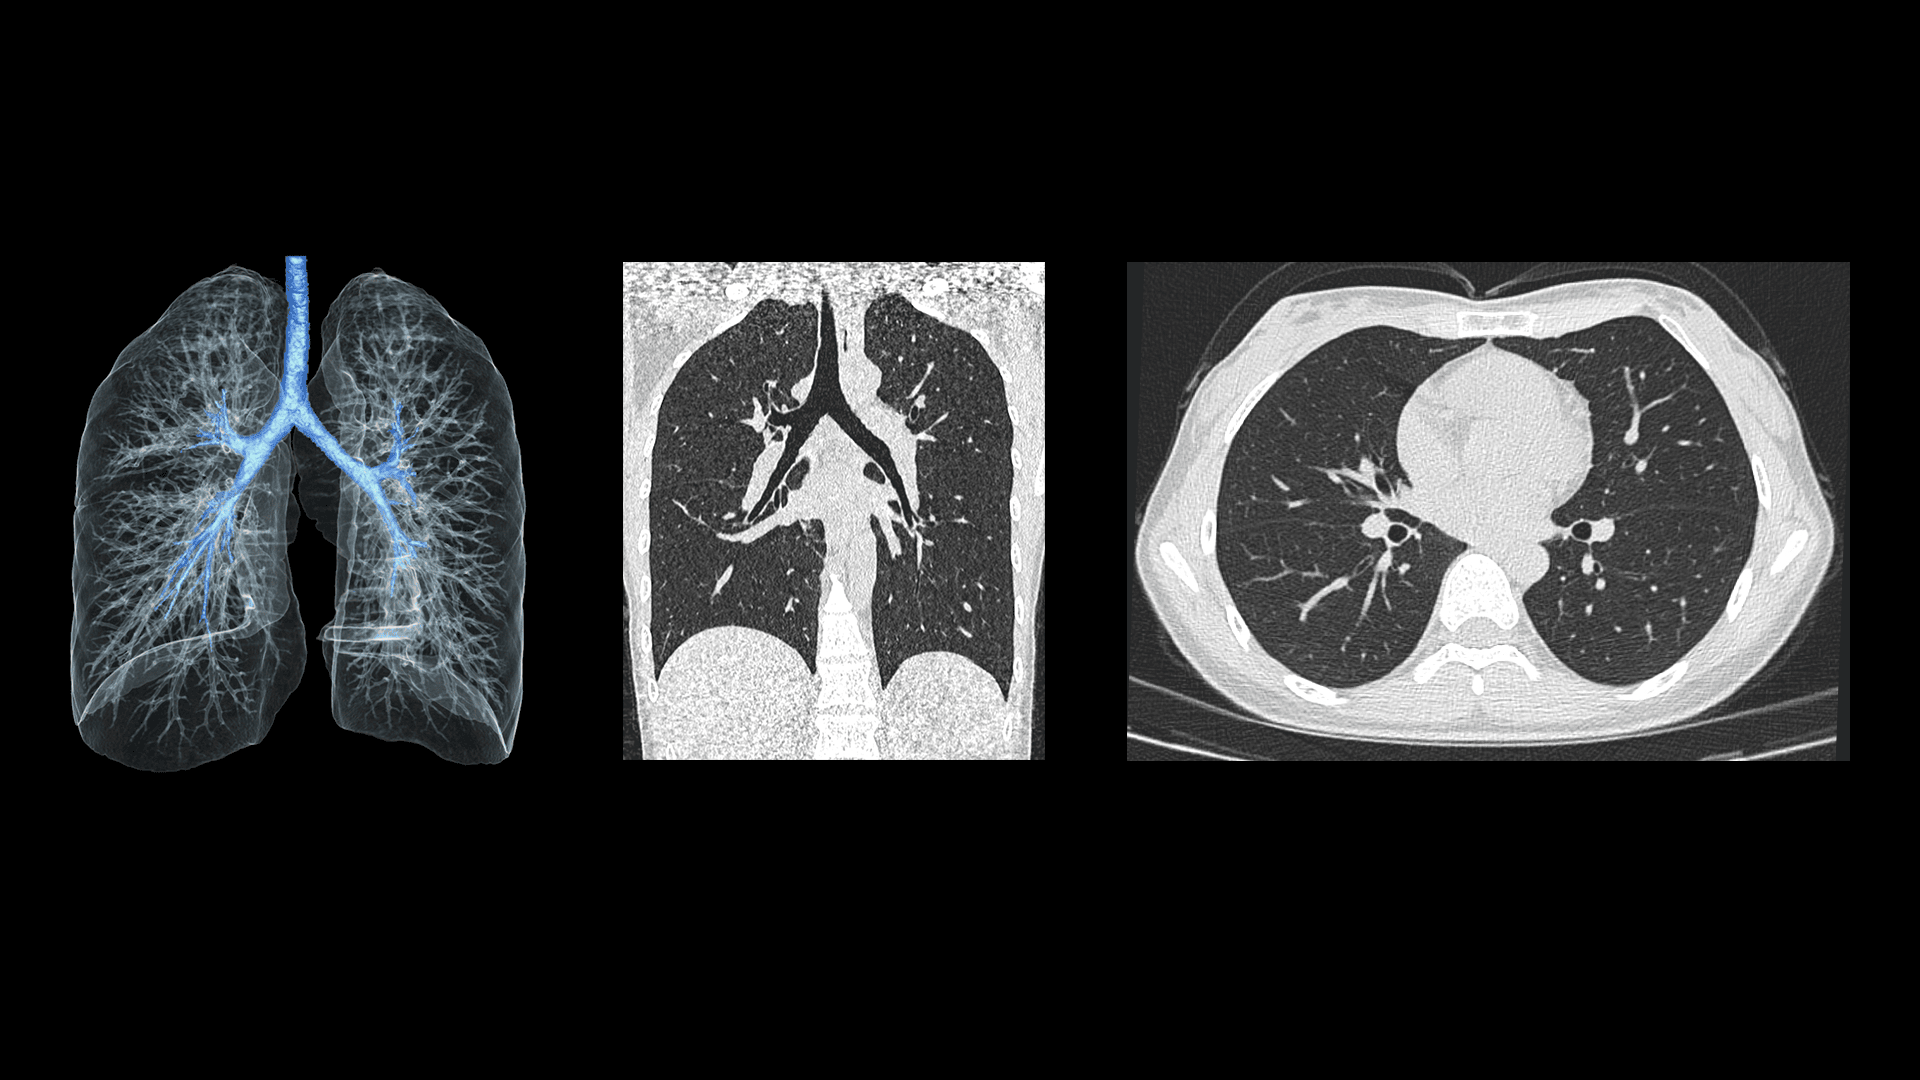

Imagistică Toracică Low-Dose la 60 kV

Pentru pacienții cu constituție slabă, tensiunea minimă de 60 kV permite reducerea semnificativă a dozei de radiații, menținând calitatea imaginii. Bronhiile principale și structurile mediastinale sunt vizualizate clar, iar reconstrucțiile MIP evidențiază precis vasele pulmonare.

| Parametri scanare |

Timp rotație: 0.71 s / rotație kV: 60 mAs: 210 CTDIvol: 1.8 mGy Doză efectivă: 0.8 mSv |

| Parametri reconstrucție |

Matrice: 512 × 512 Grosime secțiune: 1.0 × 0.5 mm HIR: B_SHARP_C WW/WL: 1500 / -500 |